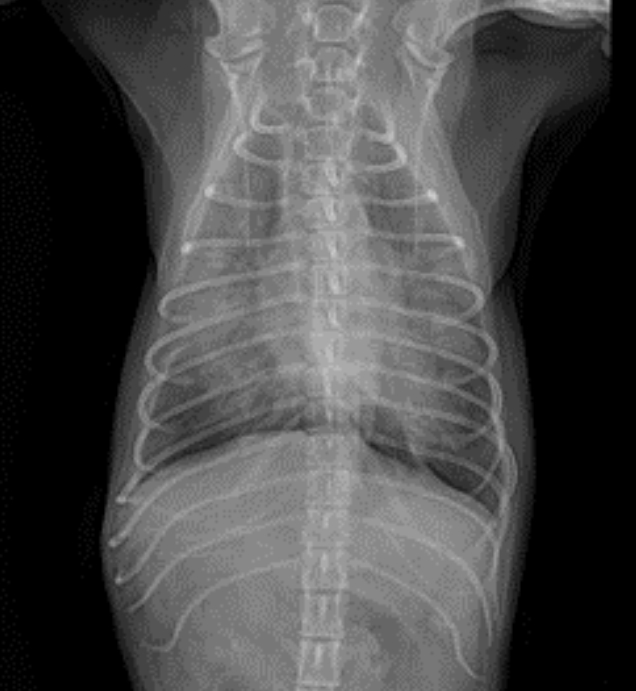

구토 이후 발생한 기침이라는 병력을 고려했을 때,가장 우선적으로 오연성 폐렴을 의심할 수 있는 상황이었기 때문에 흉부 방사선 촬영과 혈액검사를 진행했습니다. ▼

방사선 검사에서는 폐야 전반에 걸친 폐침윤이 확인되었고, 혈액검사에서는 염증 수치 상승 소견이 관찰되었습니다.

병력과 검사 결과를 종합했을 때 오연성 폐렴이 의심되었으나, 폐 병변의 범위와 정도가 비교적 심한 편이었기 때문에 다른 원인 질환에 대한 감별도 필요하다고 판단하여 보호자님께 전반적인 추가 검사를 제안드렸습니다.